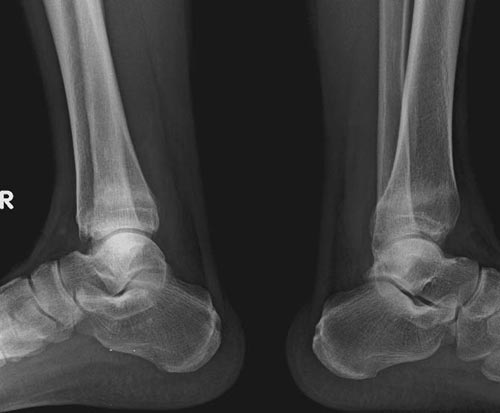

本院职工,35岁,月前稍运动后出现双踝关节疼痛,不肿,数天后出现软组织稍肿胀。风湿全套及痛风检查均未见异常。血常规正常。

x线检查月前片示双踝关节骨质未见明显异常。一月后肿胀大部消失,疼痛稍有好转,摄片示两侧骨下段条带状高密度影,边界尚清。ct扫描示两侧胫骨下段骨皮质增厚不明显,髓腔内密度显示磨玻璃样增高,髓腔显示狭窄。

双胫骨下段近骨端处可见对称性增生硬化,骨小梁增粗但纹理尚清晰,未见明显骨质破坏,临近关节及关节囊未见明显异常。

x线检查一个月前示双踝关节骨质未见异常。一个月后肿胀大部消失,疼痛稍有好转,摄片示两侧胫骨下段横行条状高密度影,边界较清。ct扫描示:两侧胫骨下段未见骨皮质增厚,两胫骨下段近骨端处可见骨小梁增粗但纹理尚清晰,未见明显骨质破坏,邻近关节及关节囊未见明显异常,软组织内未见异常.综上所诉考虑1.低毒感染所致,2.假性痛风

x线片表现为双侧胫骨下端粗条状磨玻璃样增高密度影,并可见骨皮质稍不连续。ct表现为双侧胫骨下端髓腔内磨玻璃样增高密度影,未见明显骨皮质不连续(可能与扫描体位有关)。

本例应该考虑为双侧胫骨下端应力性骨折。